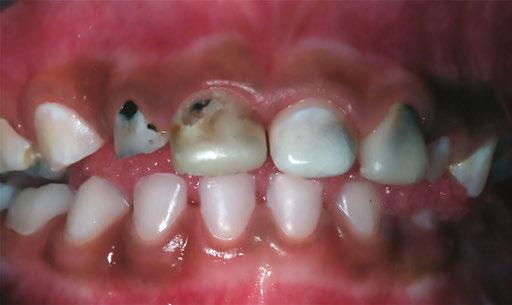

Several clinical solutions exist for primary anterior teeth with multisurface decay. Full coronal restoration of carious primary incisors may be indicated when caries is present on multiple surfaces, pulpal therapy is indicated, caries may be minor, but oral hygiene is very poor, or in a child with severe early childhood caries or a high caries risk diagnosis.1 Depending on the clinical scenario, a minimally invasive approach with the utilization of a high viscosity glass ionomer cement (HVGIC), with or without the combination of silver diamine fluoride (SDF) in a strip crown form, may pause the caries progression and provide an adequate clinical solution. Resin composite strip crowns have shown 80% retention rates and adequate parental satisfaction,1-4 although composite resin strip crowns have shown lower retention rates in teeth with decay involving three or more surfaces and particularly in children with a high caries risk4-6 (Figure 1). This could be from the continued high caries risk behaviors of the patient, as composite resin strip crowns in this population have shown to have increased inflamed marginal gingiva and gingival bleeding, increased plaque retention along the restoration, and loss of some restorative material.5,6

With parental interest increasing in esthetic treatment options for complex anterior caries, preformed pediatric zirconia crowns are becoming the treatment of choice for patients with a high caries risk or a severe early childhood caries diagnosis.14

This review discusses three clinical cases in which NuSmile® ZR (NuSmile, Houston, Texas) anterior pediatric zirconia crowns were the correct clinical decision in varying clinical scenarios.

Case 1

A 2-year-old male who received full mouth dental rehabilitation (FMDR) under general anesthesia presented for his 6-month recall at 2-year post FMDR. He had significant plaque accumulations with poor oral hygiene along his existing stainless-steel crowns (SSCs) and non-treated teeth. Additionally, the patient had gingival bleeding and gingival inflammation

22 Pediatric Dental Practice US Volume 2 Number 1 CASE REPORT

Figure 1: Occlusal films at recall visit in high caries risk patients showing loss of material and recurrent decay in composite resin strip crowns Figure

around these clinical sites. His anterior zirconia crowns showed healthy gingival margins with little-to-no plaque accumulations. This positive clinical finding is from the highly polished nature and biocompatibility of pediatric zirconia crowns. These restoration features limit plaque accumulations on the restoration and along the marginal gingiva, providing a localized positive aspect directly related to the choice of restorative material (Figure 2).